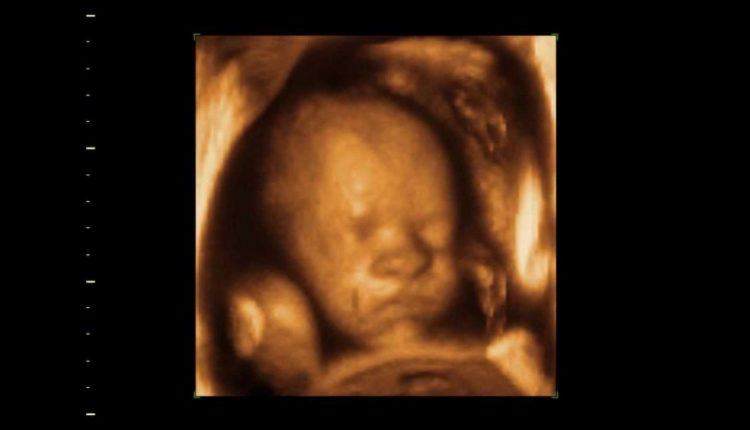

فوجئ أبوان بصورة بدت مخيفة لطفلهما المنتظر وهو في بطن أمه، خلال جلسة في معمل الموجات فوق الصوتية للاطمئنان على حالته.

وأشارت المراهقة إلى أن الطبيبة التي كانت معها خلال جلسة التصوير بـالموجات فوق الصوتية، أخبرتها أن طفلتها طبيعية وبحالة جيدة، لافتة إلى أنه من غير الغريب أن يظهر الجنين بهذا الشكل في الصور.